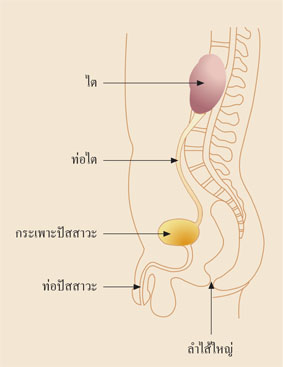

โดยทั่วไปน้ำปัสสาวะจะปราศจากเชื้อโรคและไหลผ่านท่อไตเข้าสู่กระเพาะปัสสาวะแล้วขับออกมาทางท่อปัสสาวะโดยไม่มีการไหลย้อนแต่เมื่อใดที่ทางเดินปัสสาวะเกิดการอุดตันหรือมีปัสสาวะจำนวนมากค้างอยู่ในกระเพาะปัสสาวะ ดังเช่นในผู้ที่เป็นโรคเบาหวาน นื่องจากระบบประสาทที่ไปเลี้ยงกระเพาะปัสสาวะผิดปกติทำให้ไม่สามารถบีบกระเพาะปัสสาวะให้ขับน้ำปัสสาวะออกมาได้หมด ยังคงค้างอยู่ตลอดเวลาทำให้เชื้อแบคทีเรียมีโอกาสเจริญเติบโตและแพร่พันธุ์มากขึ้นจนทำให้อาการอักเสบติดเชื้อเป็นมากขึ้น ในกรณีที่รุนแรงหรือเป็นบ่อย ๆ อาจลุกลามถึงเนื้อไตทำให้ไตเสียจนเป็นโรคไตเรื้อรังในที่สุด อาการและอาการแสดงของผู้เป็นโรคนี้ คือ ปัสสาวะแสบขัด ถ่ายปัสสาวะบ่อย ปัสสาวะขุ่น ปวดบั้นเอว ไข้หนาวสั่น คลื่นไส้ อาเจียน